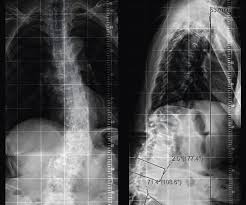

Sie werden jedoch schnell merken wieso es weh tut und dürfen keine Zeit verstreichen lassen. Während bei jüngeren Menschen fast immer Sport- oder Verkehrsunfälle ursächlich sind gehen bei älteren Menschen Wirbelbrüche oft mit Osteoporose einher. Bei instabilen Brüchen besteht dagegen die Gefahr dass Teile des Bruches die Nervenwurzel im Spinalkanal einengen und dadurch neurologische Ausfälle wie Lähmungen folgen.

Diese Wirbelbrüche sind zwar nicht instabil und die Gefahr von Schäden am Rückenmark ist sehr gering dennoch können sie starke Schmerzen und eine Fehlstellung der Wirbelsäule verursachen. Er kann an einem der sieben Halswirbel entstehen. Bei jüngeren Betroffenen sind in der Regel Verkehrs- und Sportunfälle die Ursachen für einen Wirbelbruch bei älteren Menschen geht ein Wirbelbruch vor allem auf eine schwache Knochenstruktur durch Osteoporose zurück.

Er kann an einem der sieben Halswirbel entstehen. Der erste Halswirbel wird als Atlas bezeichnet der zweite als Axis. Dieser Bereich stellt den oberen Teil der Wirbelsäule dar der aus den Wirbelkörpern Bandscheiben Muskeln Bändern und den Nervenbahnen besteht. Denn der Eingriff birgt Risiken gerade für ältere Betroffene die Operationen nicht mehr so gut verkraften. Er kann an einem der sieben Halswirbel entstehen. Die Schmerzen können einen älteren Menschen ans Bett fesseln und seiner Mobilität berauben und hier lauert die eigentliche Gefahr. Nur 15 bis 20 Prozent aller Wirbelsäulenverletzungen betreffen die Halswirbelsäule. Unter einem Genickbruch versteht man allgemein einen Bruch der Halswirbelsäule. Diese Wirbelbrüche sind zwar nicht instabil und die Gefahr von Schäden am Rückenmark ist sehr gering dennoch können sie starke Schmerzen und eine Fehlstellung der Wirbelsäule verursachen.

Beschreibung Ein Genickbruch bezeichnet einen Wirbelbruch der Halswirbelsäule. Bei einem jungen Sportler ist man eher geneigt eine Operation durchzuführen als bei einem alten bettlägrigen Patienten den man so ohne großen Nutzen für die Dauer von weiteren 2 Monaten in ein. Bei einem Wirbelbruch durch Osteoporose raten viele Ärzte zu einer Operation. Nur 15 bis 20 Prozent aller Wirbelsäulenverletzungen betreffen die Halswirbelsäule. Bei instabilen Brüchen besteht dagegen die Gefahr dass Teile des Bruches die Nervenwurzel im Spinalkanal einengen und dadurch neurologische Ausfälle wie Lähmungen folgen. Weil der Wirbelsäulenkanal der Halswirbelsäule sehr eng ist wird bei der Verletzung in 70 Prozent der Fälle zusätzlich auch das Rückenmark geschädigt. Der erste Halswirbel wird als Atlas bezeichnet der zweite als Axis.